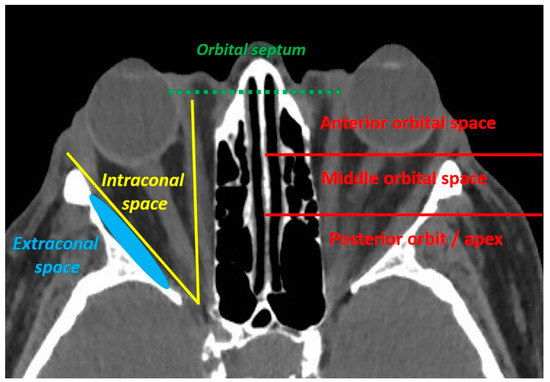

The eyelids are considered a high-risk skin malignancy area. Managing periocular tumours is challenging for functional and cosmetic reasons. Basal cell carcinoma (BCC) is the most common eyelid cancer, followed by squamous cell carcinoma (SCC), melanoma, sebaceous carcinoma and Merkel cell carcinoma (MCC) [1]. Surgery remains the mainstay of treatment for localised tumours, with the aim of obtaining clear surgical margins. Tumours originating from the internal or external canthus are at particular risk of orbital invasion [2,3]. An orbital involvement is defined as an orbital septum violation by the tumour. The orbital invasion should be classified as anterior, middle or posterior, and the extraconal or intraconal involvement should be specified (Figure 1).

Figure 1.

The orbital invasion (defined as an orbital septum violation) by an eyelid malignant tumour can be defined as intraconal (if located inside the oculomotor muscle cone) or extraconal (if located outside the oculomotor muscle cone), and should be located according to its depth (anterior, middle or posterior orbit).